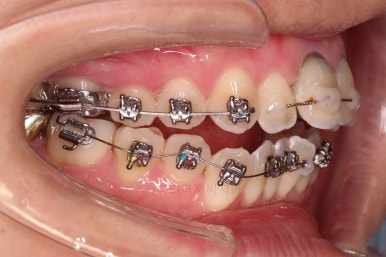

3. 치료과정

장치 부착은 윗니 어금니부터 했습니다.

미니스크류를 다양하게 활용하여 어금니 높이를 조절합니다.

여전히 앞니는 내버려둔 채로, 윗니는 어금니쪽만 진행하며 아랫니도 장치를 부착했습니다.

난이도가 매우 높은 치료인만큼 미니스크류의 구성과 장치 구성도 매우 복잡했는데요.

윗니 어금니를 뒤로 밀면서 앵글씨 2급 부정교합을 개선해 주고, 높낮이를 조절하면서 개방교합을 개선해 줍니다.

개방교합도 많이 다물어졌고, 2급 부정교합도 매우 많이 개선되었네요.

임플란트 가능 시점이 점점 다가오는데요.

임플란트를 한 번 하게되면 많은 치아 움직임은 없어야 되기 때문에, 앞니의 높이, 입매, 교합 등등 모든 점에서 평가가 진행됩니다.